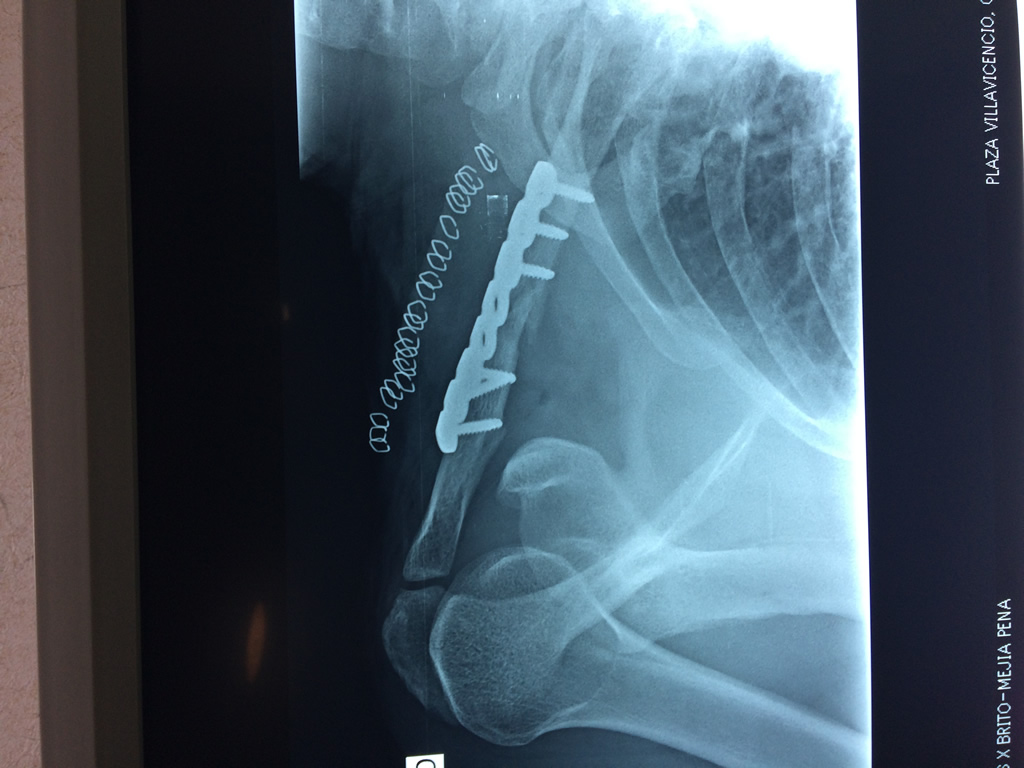

Cirugía de Fémur - Clavícula